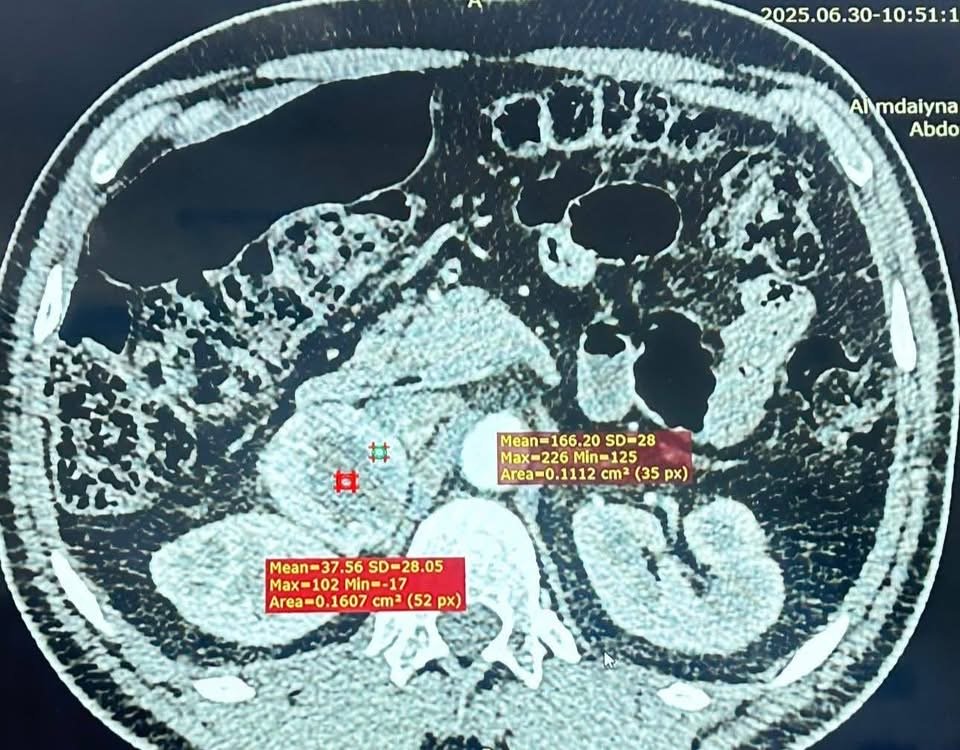

المريض، البالغ من العمر ٤٤ عامًا، راجعَ مركز الفيحاء التخصصي بعد معاناة طويلة من ارتفاع شديد في ضغط الدم وتسارع حاد في ضربات القلب. وبعد إجراء الفحوصات اللازمة، تبيّن وجود ورم كبير في الغدة الكظرية اليمنى، يفرز كميات مرتفعة جدًا من هرمون النور أدرينالين (Pheochromocytoma)، ما شكّل خطرًا كبيرًا على حياته.